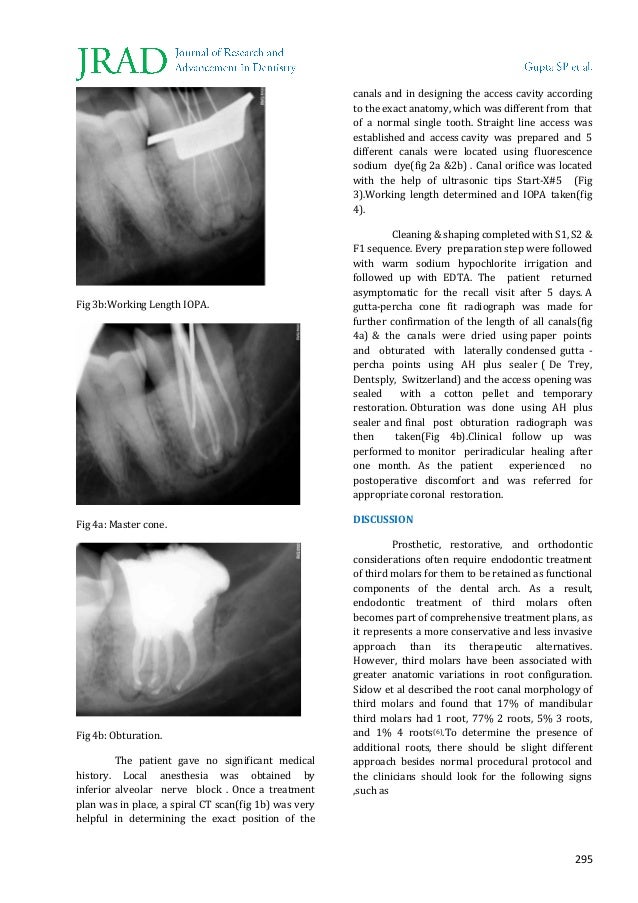

|---|---|

| FMA | 290269 |

- 5 Roots In Tooth